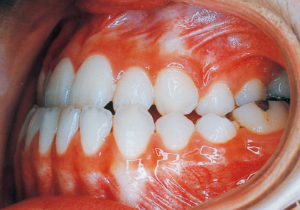

2 After Phase 2 Treatment 5-9-’92

16 5-9-’92 After Phase 2 Treatment

Afterwards, follow-up was conducted, but based on the growth pattern, surgical intervention was determined necessary, and the patient entered a period of regular observation.

Post-surgical orthodontic period: 10 months

Retention period: 2 years 5 months